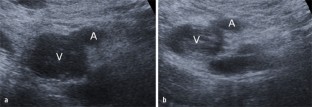

Abb. 2